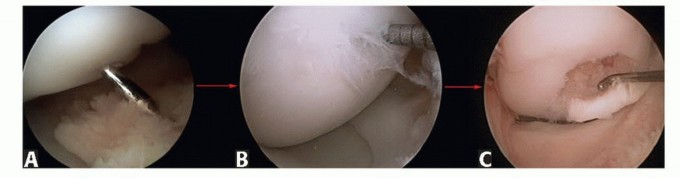

DEFINITION The terminology of osteochondral lesions is not uniform: Transchondral fractures, osteochondral fr…